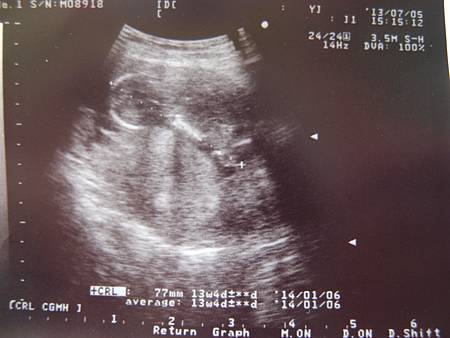

7/5 13W5D

今天看醫生囉!醫生說一切正常,照了北鼻的手腳,一隻腳彎曲翹起來,但是我怎麼看還是看不懂,北鼻長大了有7.7公分了,但是今天看起來沒有像之前一樣很好動,都沒有手足舞蹈的,聽了心跳但不是很明顯,雖然醫生說一切OK,但是北鼻今天心情不好還是不舒服嗎?沒有活力捏!我還是很擔心,不過醫生一直叫我不要太憂慮,唉真希望我做得到啊!